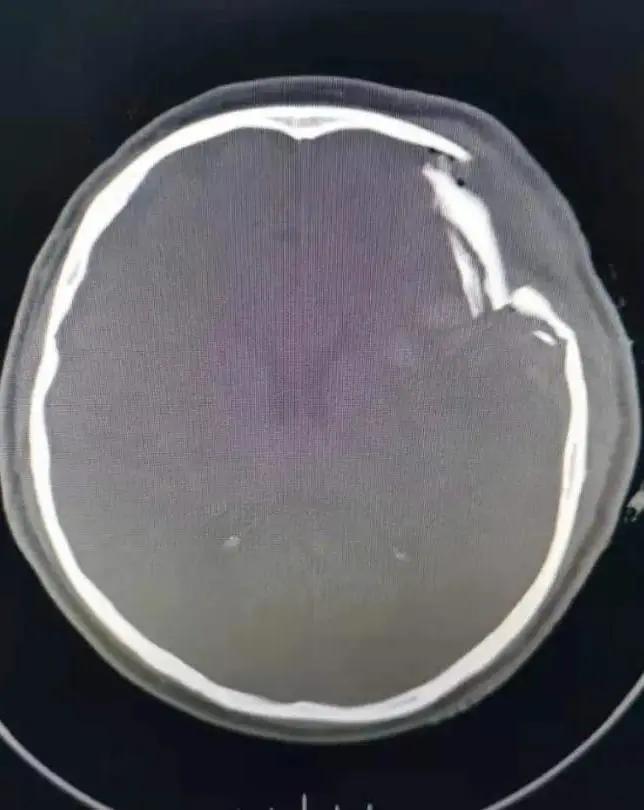

家住萧县白土镇的潘大爷在回家途中,因意外摔伤头部,急到萧县人民医院就诊,头颅CT显示:粉碎性凹陷性颅骨骨折、脑挫伤、脑内血肿。潘大爷处于昏迷状态,左颞顶部挫伤、肿胀,其上有一长约7㎝的伤口,有脑组织外溢,颅骨凹陷明显,病情危急,需急诊开颅手术,事不宜迟,必须争分夺秒。生命重于泰山,面对病人危重的病情,急诊科、神经外科医生响应迅速,立即组织专家进行综合会诊,认为患者情况危急,必须马上手术,在和家属充分沟通基础上,家属同意实施手术抢救。